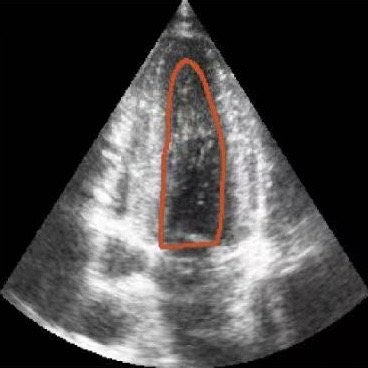

Figure 1: Illustrative challenges for echocardiography video segmentation: (a) speckle noise, (b) indistinct or blurred contours, and (c-f) the substantial changes in the target’s shape and scale throughout the cardiac cycle.

However, achieving precise segmentation in echocardiography faces severe challenges stemming from poor image quality and complex cardiac dynamics. Figures 1(a) and 1(b) show that ultrasound images are characterized by high speckle noise and low contrast, which obscure tissue structures and lead to weak or incomplete anatomical boundaries. These artifacts hinder the model’s ability to learn robust features and can result in the inaccurate segmentation. In the temporal dimension, the heart undergoes significant non-rigid deformation throughout the cardiac cycle. Figures 1(c), 1(d), 1(e) and 1(f) show that, the shape and scale of the LV change dramatically between systole and diastole. This substantial dynamic variation demands that segmentation models possess strong temporal modeling capabilities to accurately track the changing appearance of the target across the video sequence [20].